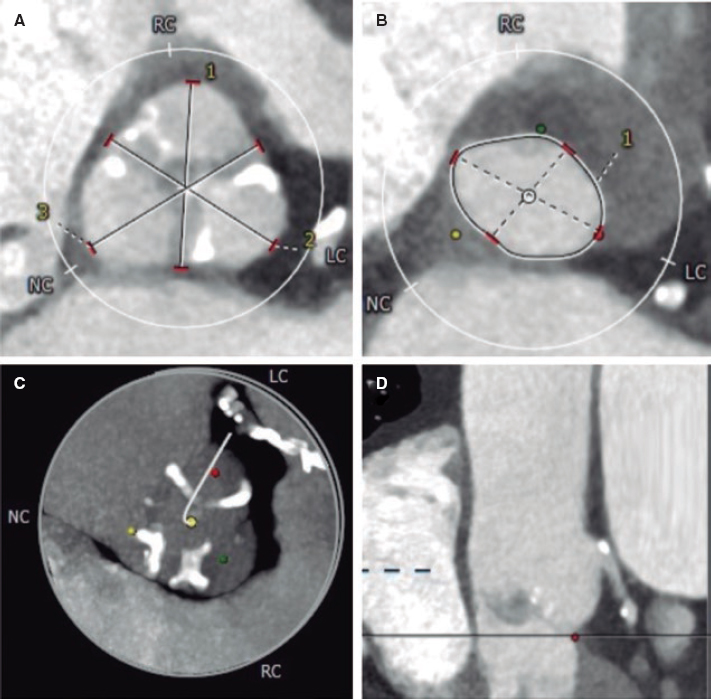

An 84-year-old female with severe aortic stenosis and previous non-disabling stroke was referred to undergo transcatheter aortic valve replacement (TAVR). The 3D computed tomography performed revealed the presence of a type 9 aortic arch with severe tortuosity (figure 1A). It was decided to protect the supra-aortic branches with suitable diameters to be able to use the Sentinel Cerebral Protection System (Boston Scientific, Marlborough, MA, United States). Manipulation length in the left common carotid artery (LCCA) was of, at least, 8 cm which is the distance between the proximal filter and the Sentinel distal edge. Figure 1B: yellow arrow: brachiocephalic trunk, 12 mm-diameter. White arrow: LCCA, 7 mm-diameter. This cerebral protection device (CPD) has a proximal filter for brachiocephalic trunk diameters between 9.0 mm and 15 mm and a distal filter for LCCA diameters between 6.5 mm and 10 mm. The angiography of the aortic arch is shown on figure 1C. This dual-system-filter basket was tried unsuccessfuly over a 0.014 in guidewire despite the use of an articulating sheath (figure 1D-F). After several attempts, a multipurpose catheter was used to engage the LCCA (figure 1G). Using a 300 cm 0.014 in guidewire, the multipurpose catheter was exchanged for the CPD which allowed its suitable deployment (figures 1H,I). The TAVR was performed successfully and the CPD was retrieved (video 1 of the supplementary data). Informed consent was obtained from the patient.

Figure 1.

The major concern is how to balance the risk of stroke after TAVR and the risk of manipulation with guidewires/catheters in supra-aortic arteries. Thus, the rigorous study of the computed tomography scan is the key factor for strategic planning purposes. This was an alternative approach to achieve the placement of a Sentinel device using a multipurpose catheter in a complex aortic arch.